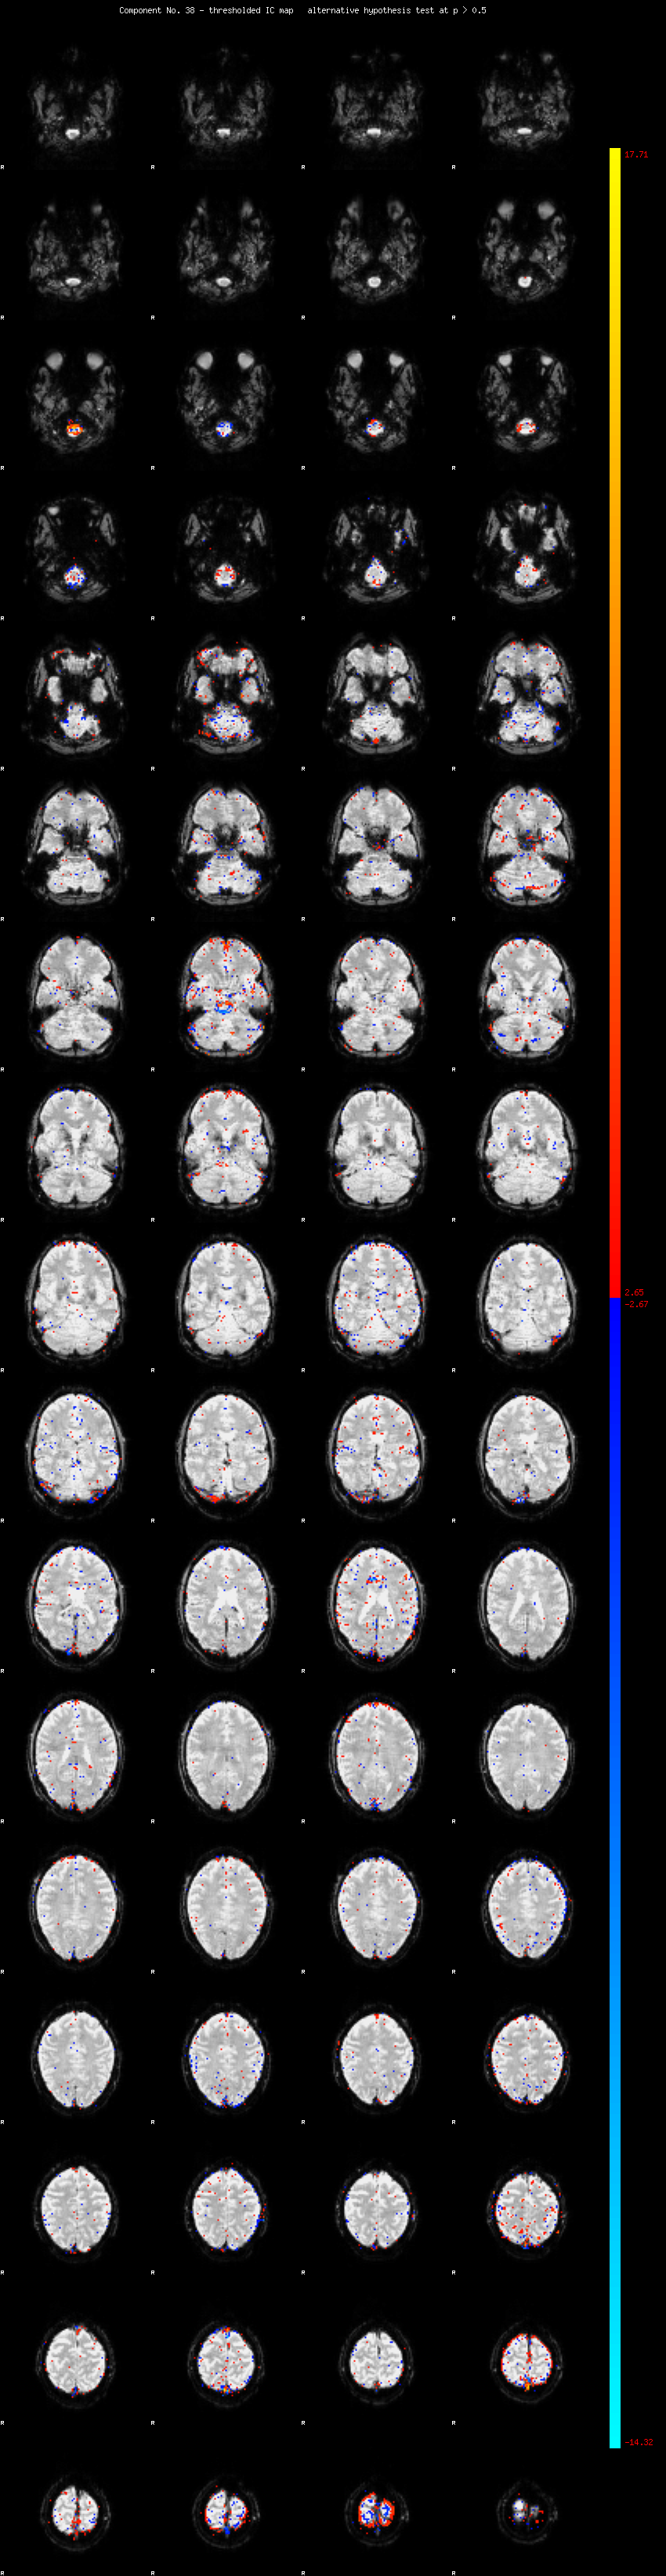

MELODIC Component 38

1.13 % of explained variance;     0.75 % of total variance

MMfit